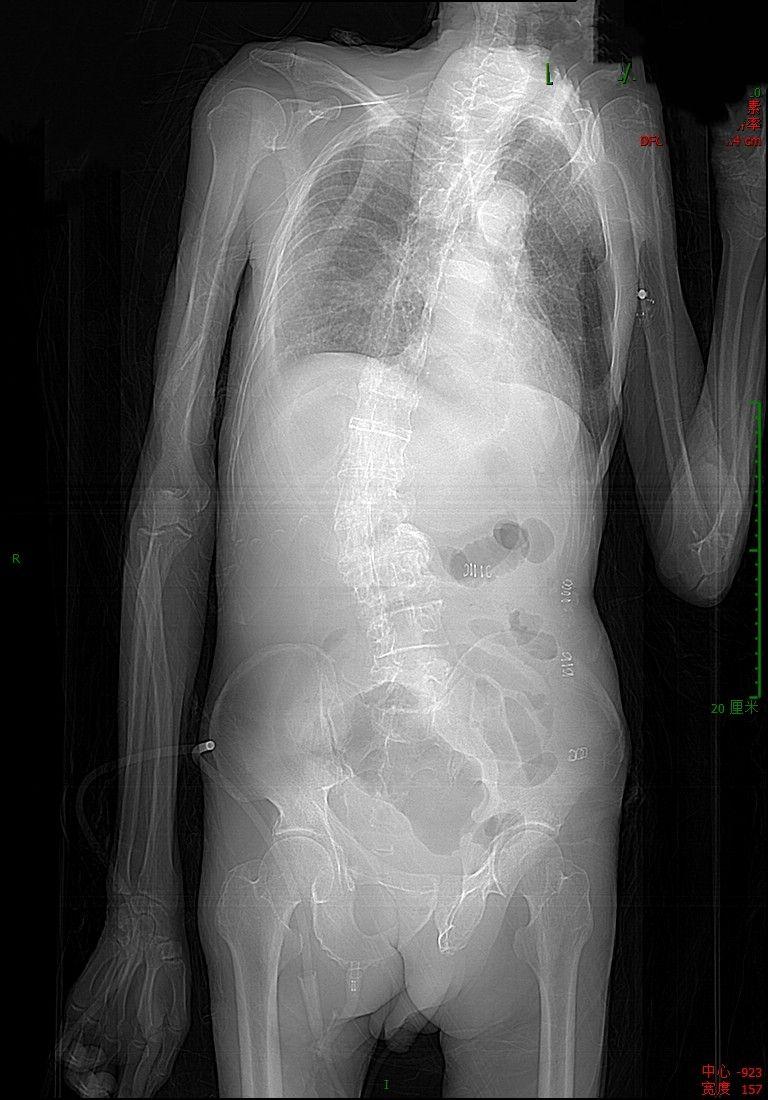

肠道淋巴瘤,最怕穿孔与梗阻,这是穿孔!